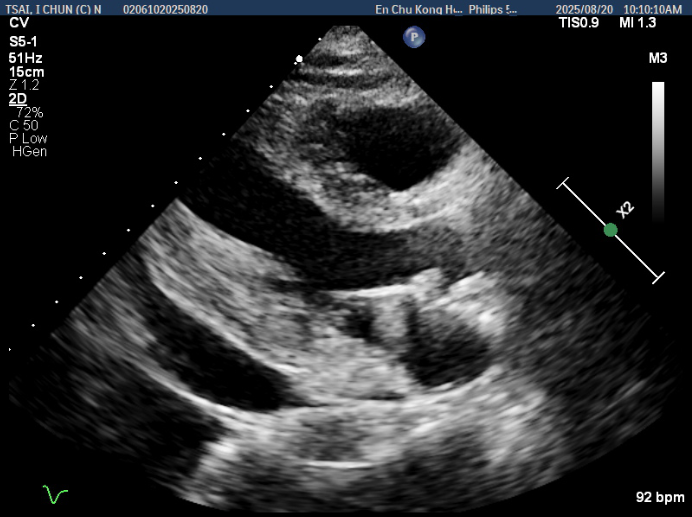

CAG identified ISR of the LAD as the culprit lesion, which was treated with a DCB. A CTO of the RCA was also noticed. A complete revascularisation strategy was planned, and she subsequently underwent a staged PCI three months after the index procedure. ECG showed sinus rhythm with chronic ST depression in the lateral leads. Transthoracic echocardiography revealed a LVEF of 65.2% without RWMA or significant valvular disease. A moderate amount of pericardial effusion was also noted.

Current angiography showed ISR of the proximal LAD. Regarding the RCA CTO, the J-CTO score was 3 based on lesion calcification, long lesion length, and bending. Collateral circulation was observed through septal collaterals from the LAD and epicardial collaterals from the left circumflex artery, classified as Werner CC2 and J-channel score 0.